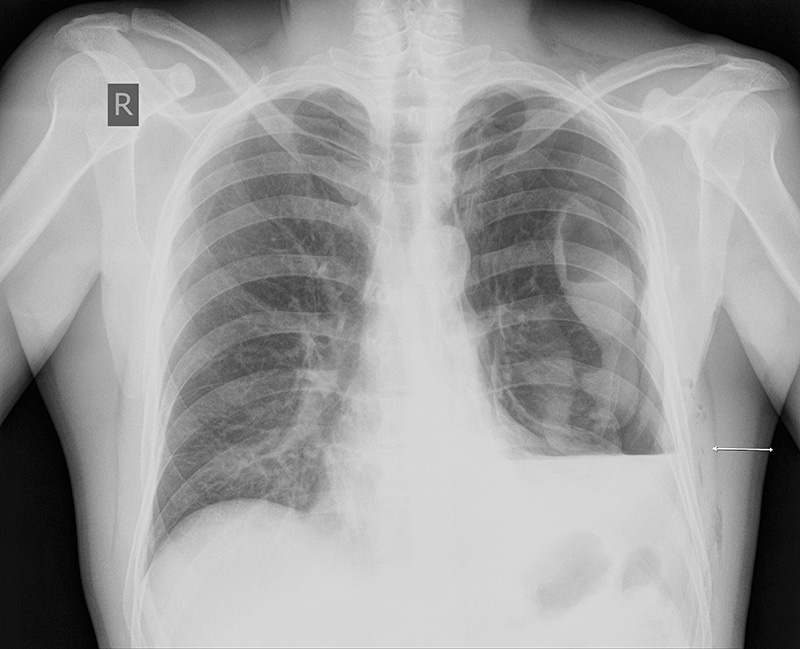

Изучение дозы излучения при рентгеновских исследованиях: визуализация